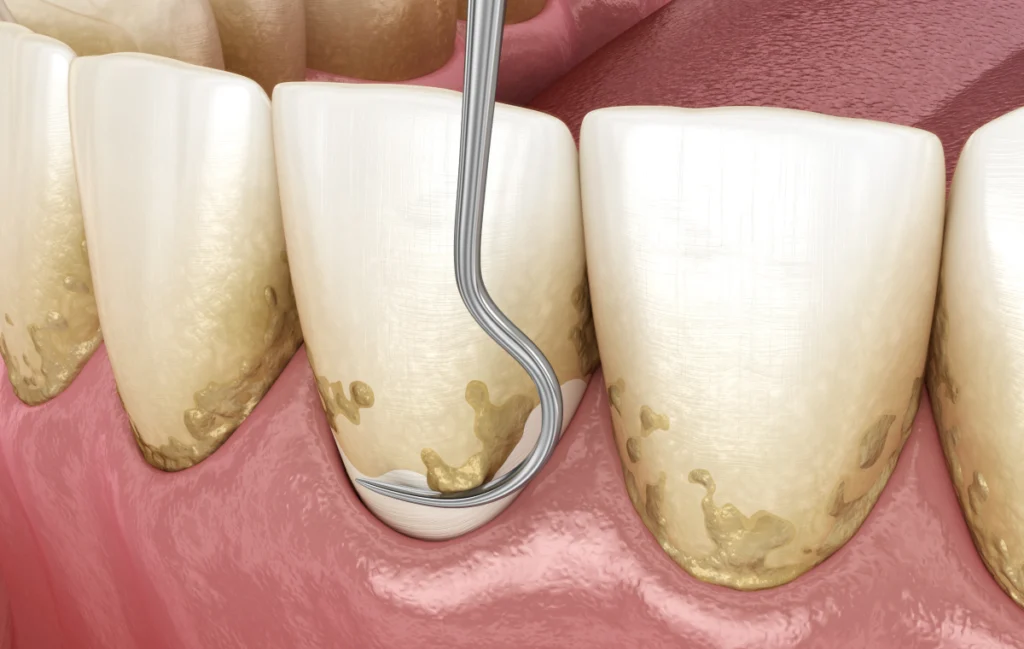

L’hygiène bucco-dentaire pré-opératoire

Une hygiène bucco-dentaire rigoureuse est indispensable avant une intervention. Il est conseillé de se brosser les dents soigneusement deux à trois fois par jour, y compris le jour de l’intervention, sauf indication contraire. L’utilisation d’un bain de bouche antiseptique dans les jours précédents peut également être préconisée pour réduire la flore bactérienne.

Un nettoyage professionnel (détartrage) réalisé quelques jours avant la chirurgie peut parfois être recommandé afin d’optimiser la santé des gencives.